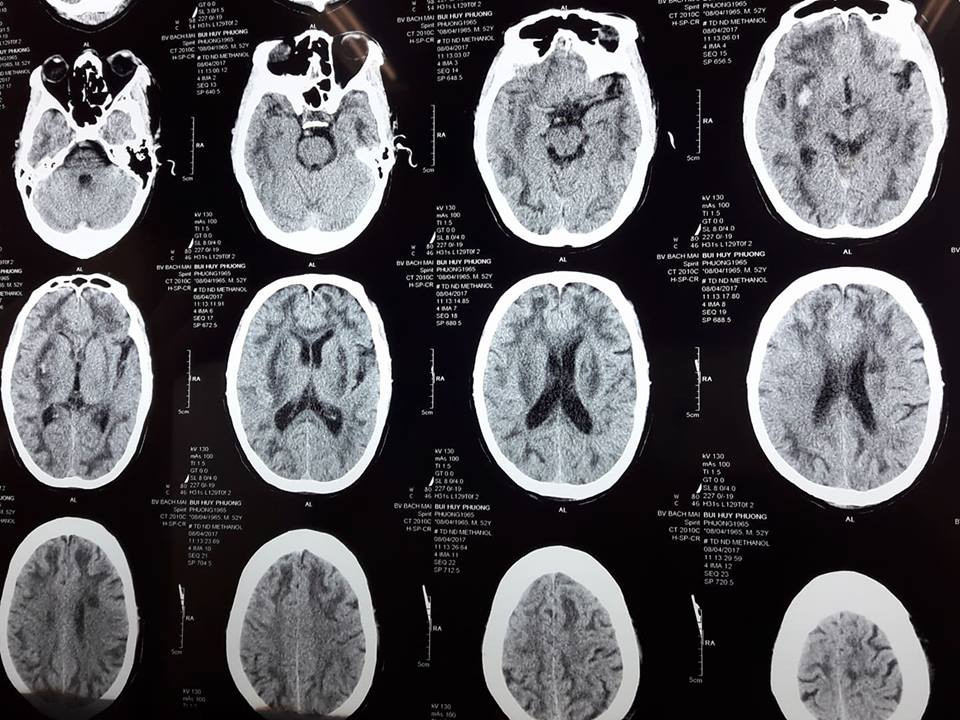

Bệnh nhân được chuyển đến Trung tâm chống độc trong tình trạng hôn mê sâu, tổn thương cả 2 bên bán cầu não, toan chuyển hoá nặng, nồng độ methanol là 45mg/dl.

Hình ảnh chụp não bị tổn thương do ngộ độc rượu có methanol của người đàn ông 52 tuổi